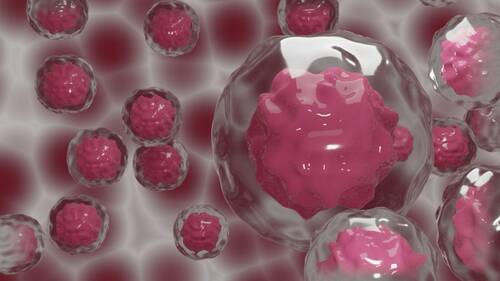

Stem Cell Therapy

Stem cell therapy is a key part of what practitioners of regenerative medicine in Chicago offer. It taps into your body’s own repair kit to fix damage from the inside out, using mesenchymal stem cells (MSCs) that the body utilizes to create specialized tissue. When these cells are concentrated and guided into a stiff or painful joint, they signal the body to quiet down chronic inflammation and start the process of tissue repair.

This is a total game-changer for the many people across the Chicago area dealing with osteoarthritis. A 2025 review and meta-analysis in Frontiers in Cell and Developmental Biology found that MSC therapy significantly lowered pain levels, with patients seeing the best results around two years after treatment.2 The results of this method depend heavily on the quality of care you receive, so consulting reputable providers specializing in these advanced biologics is essential. when considering stem cell therapy for knee pain, for instance, it’s importsn to consult reputable providers specializing in these advanced biologics.